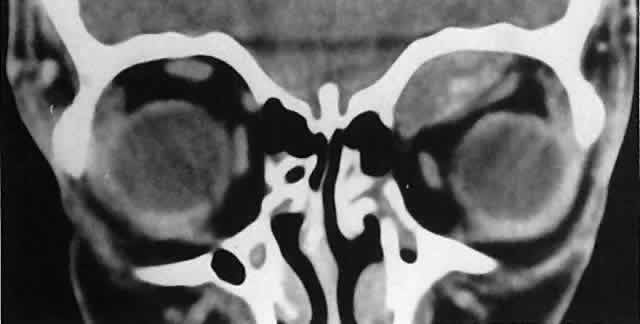

In dacryoadenitis, external inflammatory signs are localized to the superotemporal quadrant, and CT shows enlargement of the lacrimal gland (Fig. 24). Lacrimal gland inflammation may be bacterial, viral, or a variant of IIPT. It is possible, however, that many cases of “idiopathic” dacryoadenitis represent unidentified viral infections. In bacterial dacryoadenitis, a leukocytosis with a left shift may be present.96 In questionable cases, a 1-week course of oral antibiotics can be administered to these patients. Among children, the probability that an enlarged lacrimal gland represents neoplasia rather than inflammation is lower than among adults, although epithelial lacrimal gland tumors occasionally may occur in the pediatric population and can produce external inflammatory signs. If the general signs and symptoms of IIPT are lacking, a biopsy should be performed.

Fig. 24. A. Nonbacterial dacryoadenitis may be unilateral or bilateral. External inflammatory signs are maximal in the superotemporal quadrant. B. The left lacrimal gland is enlarged, with a shape molded by the globe and orbital walls. A neoplasm usually can be ruled out by analysis of the history, CT findings, and echographic characteristics, but a biopsy may be required in equivocal cases.